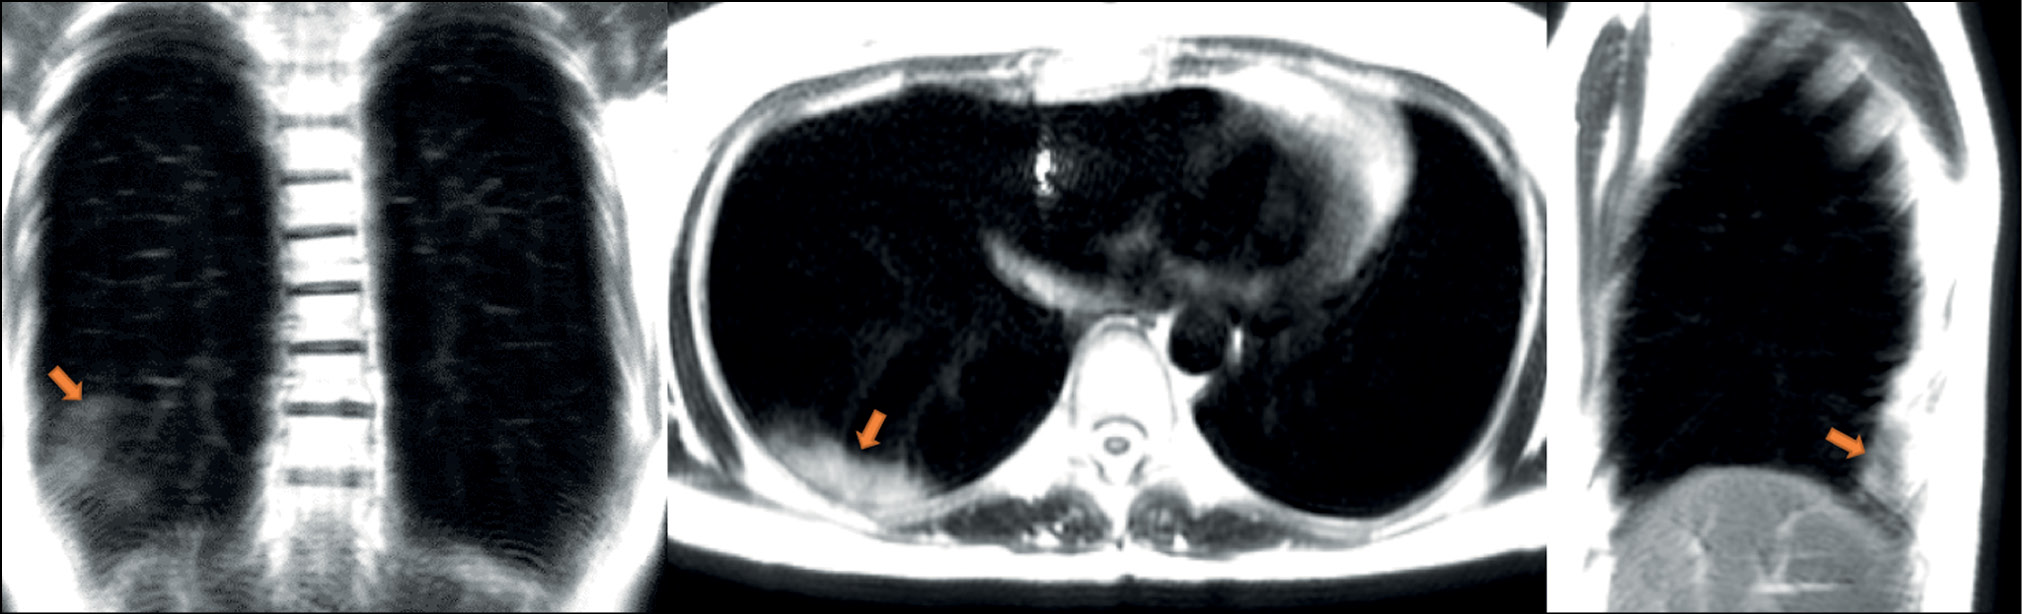

A patient (female, 25 years old) complained of a dry cough, high fever (up to 39°С), chills, and chest heaviness. She went to the hospital on the sixth day after the onset of the first symptoms, when they became extremely pronounced. Dynamic MRI showed a large area of increased signal in segments S6, S8, and S9 of the left lung’s lower lobe. An inhomogeneous increased signal was found during inhalation in the coronal, axial, and sagittal planes (Fig. 3). The signal intensity increased in the coronal and sagittal planes during exhalation (Fig. 4), with the increased visual size of the affected areas and the expanded “cloudy sky” area. These findings may be attributed to expiratory contraction of lung tissue during exhalation.

Figure 3. Dynamic magnetic resonance imaging of the lungs during inhalation in the coronal, axial, and sagittal planes. Orange arrows point to consolidation areas visible during inhalation (S6, S8, and S9). The white arrow points to the area with the “cloudy sky.”